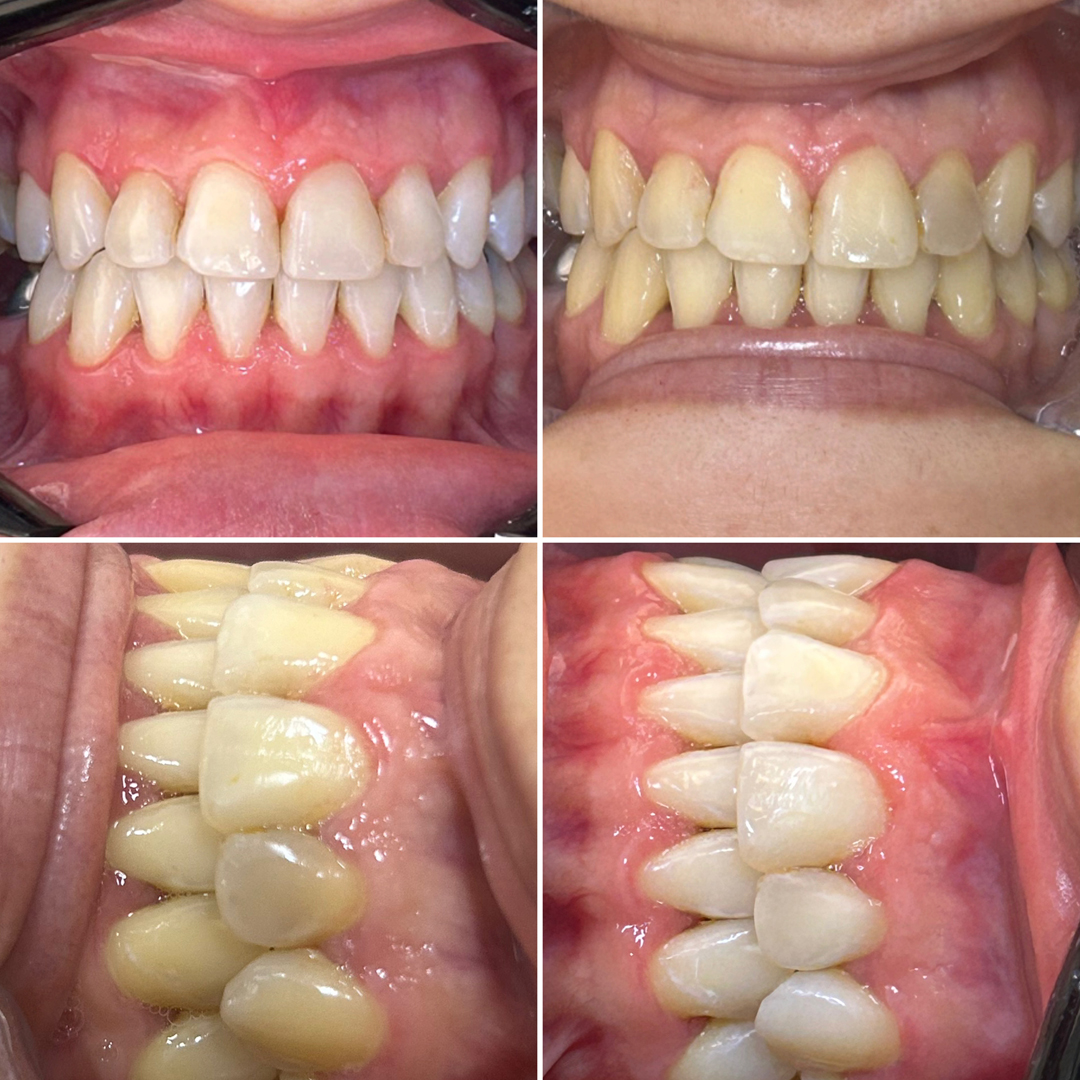

Reabilitação Oral e estética

● Coroas unitárias em cerâmica

● Pontes fixas em cerâmica

● Lentes de contato/laminados cerâmicos

Reabilitação Oral e estética (Coroas unitárias em cerâmica)

Pontes fixas em cerâmica

Lentes de contato/laminados cerâmicos